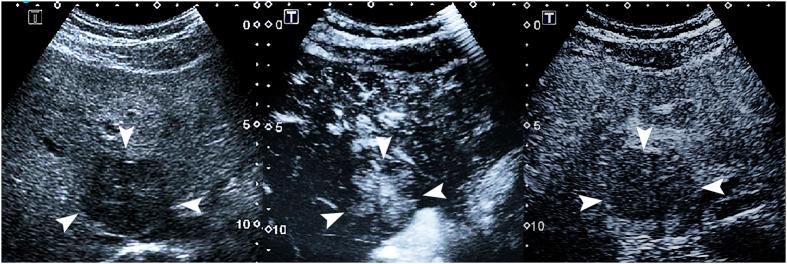

To evaluate the diagnostic performance of quantitative analysis as an adjunctive diagnostic tool to contrast-enhanced ultrasound (US) for the differentiation of atypical benign focal liver lesions (FLLs) from malignancies in fatty liver. Twenty-seven benign FLLs and fifty-six malignant FLLs that appeared hyper-enhanced during the arterial phase with washout in the portal or late phase in fatty liver were analyzed. Chi-square tests and logistic regression were applied to identify the specific features. Three sets of criteria were assigned: 1) all FLLs subjected to routine contrast-enhanced US; 2) all FLLs subjected to quantification analysis and contrast-enhanced US; and 3) parts of FLLs that could not be diagnosed using contrast-enhanced US (n = 66, 75.9%) but instead were diagnosed using parametric features. The sensitivity, specificity, accuracy and area under the receiver operating characteristic curve (AUC) of the three sets of criteria were analyzed. The AUCs of the criterion set 2 were significantly higher than those of criterion set 1 (0.904 versus 0.792, P = 0.008). Criterion set 3 showed a relatively high sensitivity (90.2%) with a relatively high AUC (0.845). The quantification analysis offers improved diagnostic performance for the differential identification of atypical benign FLLs from malignancies in fatty liver.

评估定量分析作为超声造影(US)辅助诊断工具,用于鉴别脂肪肝中不典型良性局灶性肝病变(FLLs)与恶性病变的诊断性能。分析了27例良性FLLs和56例恶性FLLs,这些病变在脂肪肝的动脉期呈高增强,在门静脉期或延迟期有廓清。应用卡方检验和逻辑回归来确定具体特征。设定了三组标准:1)所有FLLs均接受常规超声造影检查;2)所有FLLs均接受定量分析和超声造影检查;3)部分无法通过超声造影诊断的FLLs(n = 66, 75.9%),而是使用参数特征进行诊断。分析了这三组标准的敏感性、特异性、准确性和受试者操作特征曲线下面积(AUC)。标准组2的AUC显著高于标准组1(0.904对0.792,P = 0.008)。标准组3显示出相对较高的敏感性(90.2%)和相对较高的AUC(0.845)。定量分析为鉴别脂肪肝中不典型良性FLLs与恶性病变提供了更好的诊断性能。